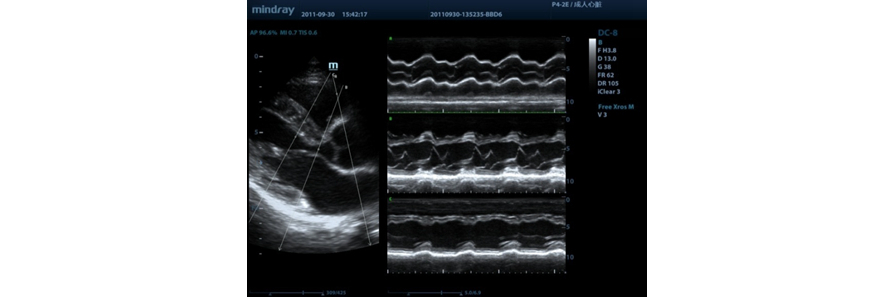

Free Xros M?

Gain precise anatomical observation by freely placing sample lines at any angle. Attain better images through simultaneous display of up to 3 sample lines.